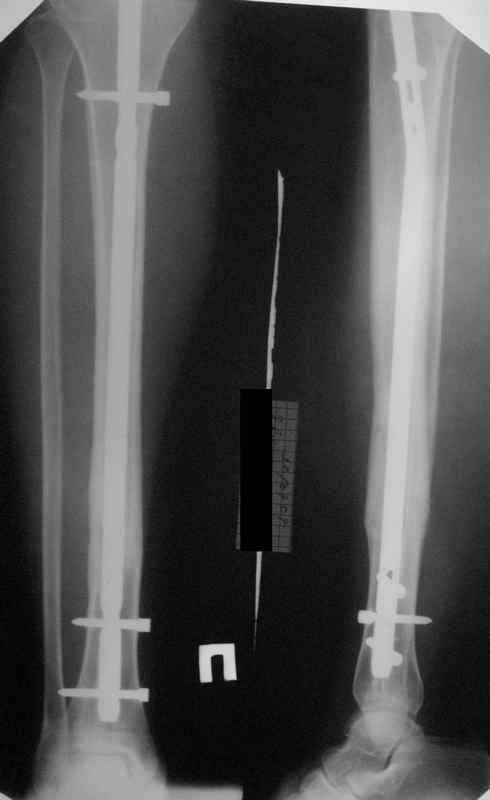

[Ortho] неправильно фиксированный перелом

Вот именно количественный, т.е. сколько градусов в вальгусе допустимо и при каком диастазе в мм или в % от толщины диафиза.

Но почему решение динамизировать на сроке 8 недель с полным удалением всех проксимальных винтов даже не рассматривается Вами? Ведь тогда нагрузка с фиксатора будет снята, и переломов  металла можно будет не бояться и наступать   полной нагрузкой.

И еще. Вам не нравится когда предлагаемое решение аргументируют типа: "а у меня было 3 пациента и у всех  у них (после такого то лечения) все харашо( или все плохо). Разносите таких аргументаторов в пух и прах. А сами этим приемом пользуетесь :(. Можете Вы сказать  без глубокой статистики : в нашем учреждении пролечено N колво больных с оскольчатыми переломами в/3, с/3, н/3 диафиза ББК и с оставленным послеоперационном вальгусом менее 3 градусов и у всех них или у M числа пациентов были 1. переломы фисаторов до сращения 2. проблемы со сращением 3. проблемы с со смежными суставами на отдаленных сроках.

Все это к тому, что те, кто занимается гвоздями и Вы в том числе можете выложить не один снимок с подобными диастазами и вальгусами-варусами, где достигнуто сращение и не получено проблем. Тогда откуда такая "адназначность" врешении об реостеосинтезе?